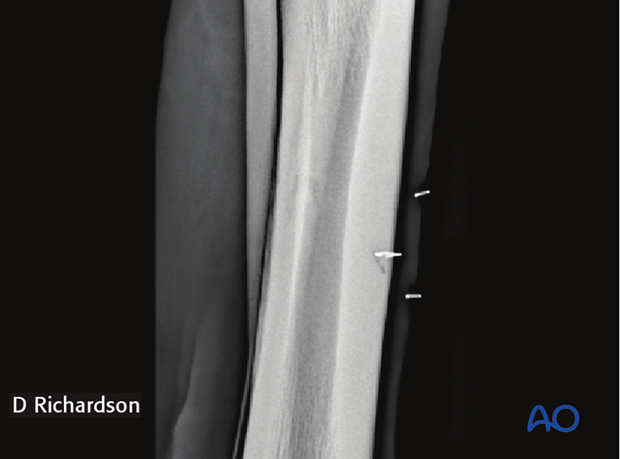

The incision is centered over the palpable swelling if it can be identified. If the fracture cannot be palpated, a small grid of sterile skin staples can be placed following aseptic preparation of the surgical site and a radiograph taken to identify the exact location for the incision.